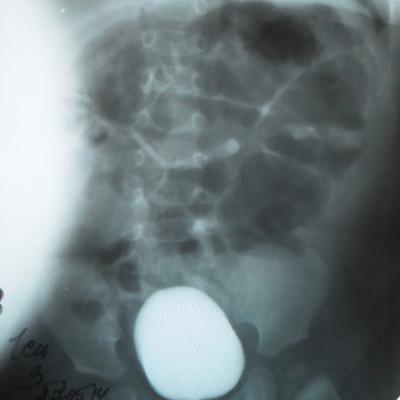

Моему ребенку 1 год 1 месяц. Во время беременности у плода было обнаружено увеличение лоханки слева - 9мм. Далее по результатам УЗИ после рождения максимальное увеличение достигало 17 мм. В 5 месяцев проходили урологическое обследование, результаты цистографии: мочевой пузырь округлой формы. Контуры ровные. ПМР нет. ЭЭД-1,2МЗВ; урографии: рентгеноконтрастных теней конкремента нет, почки в типичном месте, размеры сохранены, структура ЧЛК справа не изменена, слева пиелоэктазия, подвижность допустима, функция сохранена, ЭЭД – 0,4 МЗВ. По последнему УЗИ (1 год) увеличение лоханки слева - 28 мм. Мочеточники и сама почка в норме. Результаты анализов мочи за этот год хорошие (сдавали ежемесячно). В чем могут быть причины данного явления и чем это грозит малышу?

Ответ врача

В данном случае - сужение лоханочно-мочеточникового сегмента и\или добавочный сосуд(слева). Но выделительная функция почки сохранена. В данный момент целесообразно наблюдение, но в дальнейшем - не исключено хирургическое вмешательство.